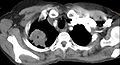

Following the initial imaging, a CT scan or MRI is preferred since both can provide more details and information such as size, lymph node involvement and other areas of invasion, such as vascular involvement.[15][10]